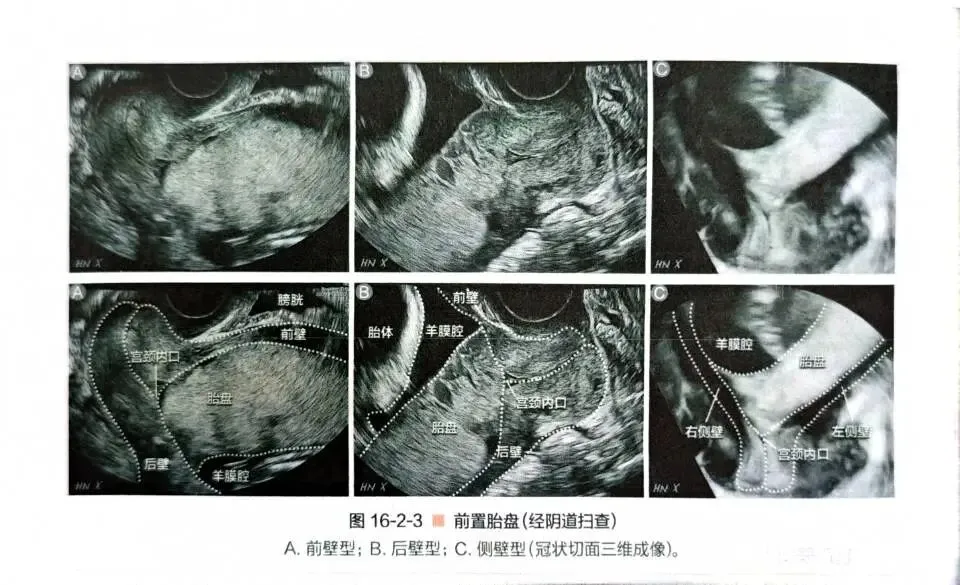

【超声扫查方法】可以经腹部、经阴道和经会阴扫查。

经阴道扫查,能够清晰显示宫颈内口与胎盘的位置关系,准确测量胎盘跨过宫颈内口的距离,任何时候怀疑胎盘前置,都建议选择经阴道超声检查。

【图例】